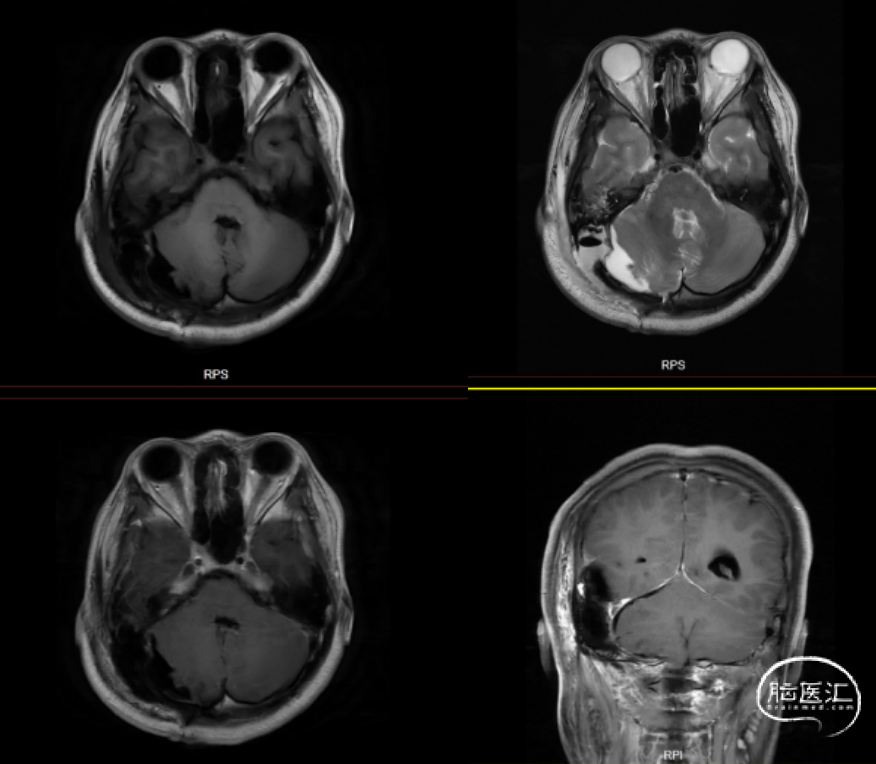

病理科讨论意见:结合该年轻患者的临床表现、影像特征及常规病理结果,得出如下鉴别诊断(图7):

1. 软骨粘液样纤维瘤(Chondromyxoid fibroma,CMF):青少年好发的良性骨内肿瘤,以黏液背景、鸡爪样血管及FOS/FOSB基因重排为特征。

2. 间叶源性肿瘤:源自间叶组织的异质性肿瘤群,涵盖良性至高度恶性亚型,免疫表型及分子变异多样(如平滑肌肉瘤、脂肪肉瘤等)。

3. 软骨源性肿瘤:以软骨分化为特征的肿瘤,如S100阳性的软骨母细胞瘤(青少年骨骺)或异型性明显的软骨肉瘤(中老年,IDH基因突变)。

本例患者为18岁女性,以头晕为主要症状,结合其年龄特征(10-30岁为颅内CMF高发年龄段)及影像学表现(边界清晰的溶骨性病变伴斑点状钙化),需优先考虑软骨源性或间叶源性肿瘤。病理学分析显示肿瘤呈分叶状结构,含丰富粘液样基质及温和的梭形细胞,核分裂象罕见,Ki-67增殖指数低(1%+),提示肿瘤恶性程度低。免疫组化结果中S-100阴性、缺乏典型组织学特征(格子样钙化、核沟、破骨巨细胞)及部位不典型排除了软骨母细胞瘤。同时,异型性缺乏及上皮膜抗原(Epithelial membrane antigen,EMA)阴性进一步排除了软骨肉瘤和间叶源性恶性肿瘤(如粘液纤维肉瘤)。尽管未检测FOS/FOSB基因重排,但结合“鸡爪样”血管模式及低侵袭性生物学行为,最终诊断为CMF。

图7. 颅内CMF与间叶及软骨源性肿瘤特征对比。